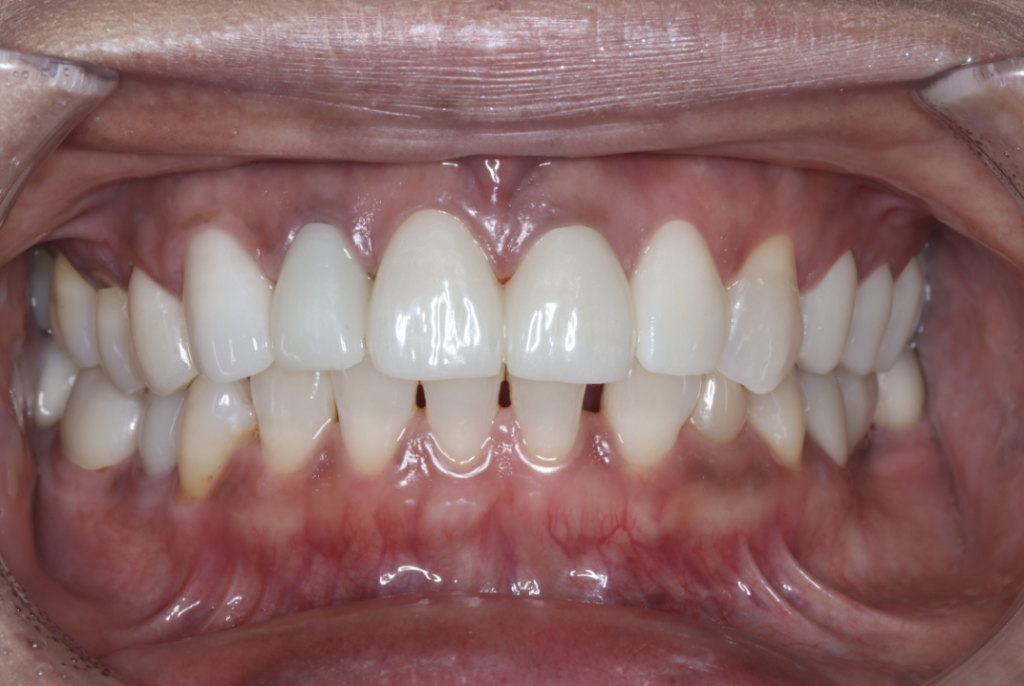

セラミック症例①

年齢40代女性

治療期間1ヶ月

治療内容ジルコニア、セラミックインレー、セラミッククラウン

治療箇所左上1番、2番 左下5番、7番 右上1番、2番、3番、4番、5番 右下5番、6番、7番

治療費用100,000円